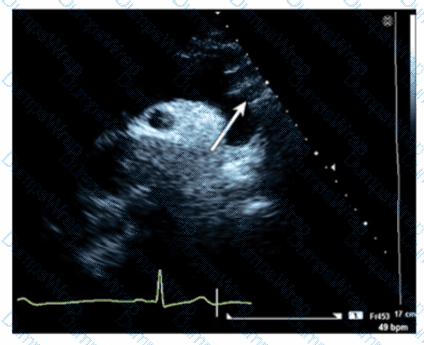

Which wall is indicated by the arrow on this video?

DExplanation:

Comprehensive and Detailed Explanation From Exact Extract:

The apical two-chamber echocardiographic view displays the inferolateral wall (also called posterior lateral). The arrow points to this inferolateral segment, which is located inferiorly and laterally in the left ventricle.

Anteroseptum and inferoseptum relate to the interventricular septum, while anterolateral is the anterior lateral wall, opposite the inferolateral wall. Correct regional wall motion assessment is essential for ischemic disease evaluation.

This identification and terminology are described in ASE stress echocardiography and chamber quantification guidelines【12:ASE Stress Echocardiography Guidelines†p.310-315】【16:Textbook of Clinical Echocardiography, 6e†p.380-385】.